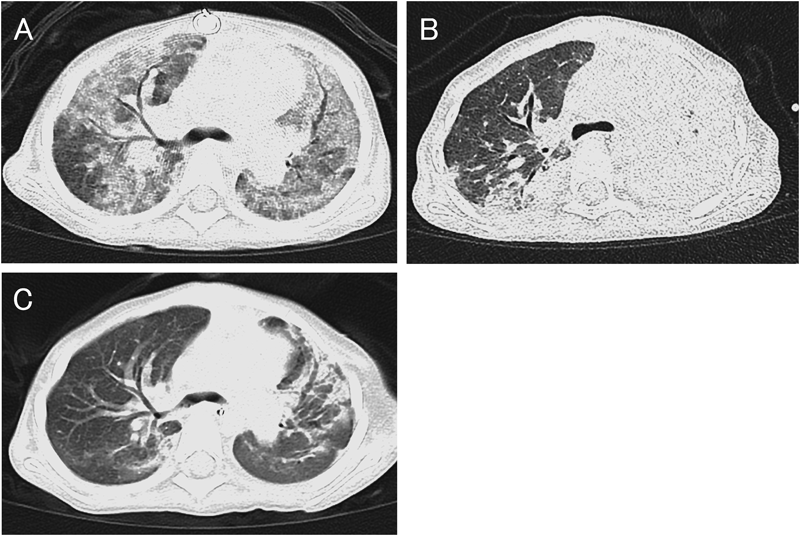

造影所見では肺動脈分岐部は著しく狭窄し,その部分に吻合したシャント血管は閉塞しかかっていた.肺動脈の形態と内径から,Glenn手術も可能と考えられたが(Fig. 1),同時に撮影した頭部CTで軽度の脳浮腫が認められたため,同手術は施行せず.日齢82にシャント交換手術(4.0 mm ePTFE)および肺動脈形成術を施行した.手術後は順調にECMOを離脱できた.

Fig. 1 CT angiograms of Case 1

(A, B) MIP images (0.75 mm thick) show stenosis of the bilateral pulmonary arteries. The junction of the RPA–BT shunt junction is the most stenotic. (red line: 2 mm). (C, D) The inner lumen of the shunt is not enhanced with contrast medium (arrow). A: aorta, LPA: left pulmonary artery, RPA: right pulmonary artery.